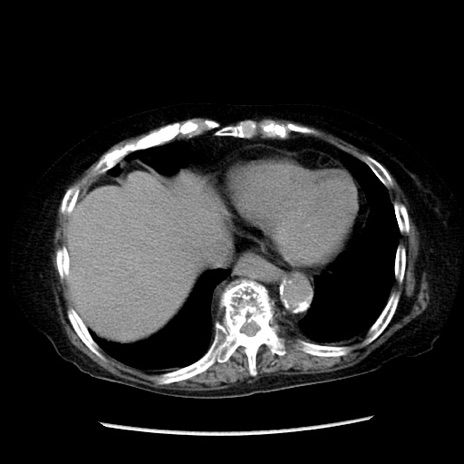

症例14(横断像)

【症例】 90歳代女性

【主訴】 腹痛・嘔吐

【現病歴】今朝から左側腹部痛を認めた。 経過観察していたが、嘔吐を認めたため来院。

【既往歴】 子宮癌術後

【身体所見】 意識清明、BP 127/54mmHg、P 98bpm Sp02 95%(RA)、BT 35.8°C、腹部平坦・軟腸ぜん動音聴取良好、右下腹部圧痛(+) 反跳痛なし

【データ】WBC 9800、CRP 0.46